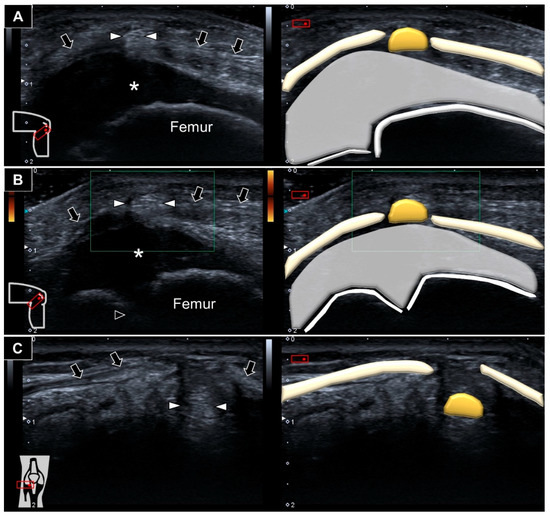

Ultrasound imaging showed an ill-demarcated hyperechoic mass protruding next to the cartilage overlying the distal femur towards the subcutaneous layer through a slit over the lateral patellar retinaculum (Figure 3A and Video S1). No increased vascularity was visualized inside or surrounding the lesion (Figure 3B). Repositioning the knee back to extension while lying supine, the mass was seen sinking to the space underneath the lateral patellar retinaculum (Figure 3C). Accordingly, herniation of the fat pad through a defect in the lateral patellar retinaculum was diagnosed.

Figure 3. Hyperechoic fat pad (white arrowheads) was seen protruding through a defect in the lateral patellar retinaculum (black arrows) (A). There was no vascularity surrounding or inside the protruded fat pad during squatting (B). The fat pad was visualized sinking underneath the lateral retinaculum upon knee extension (C). *: hyaline cartilage.